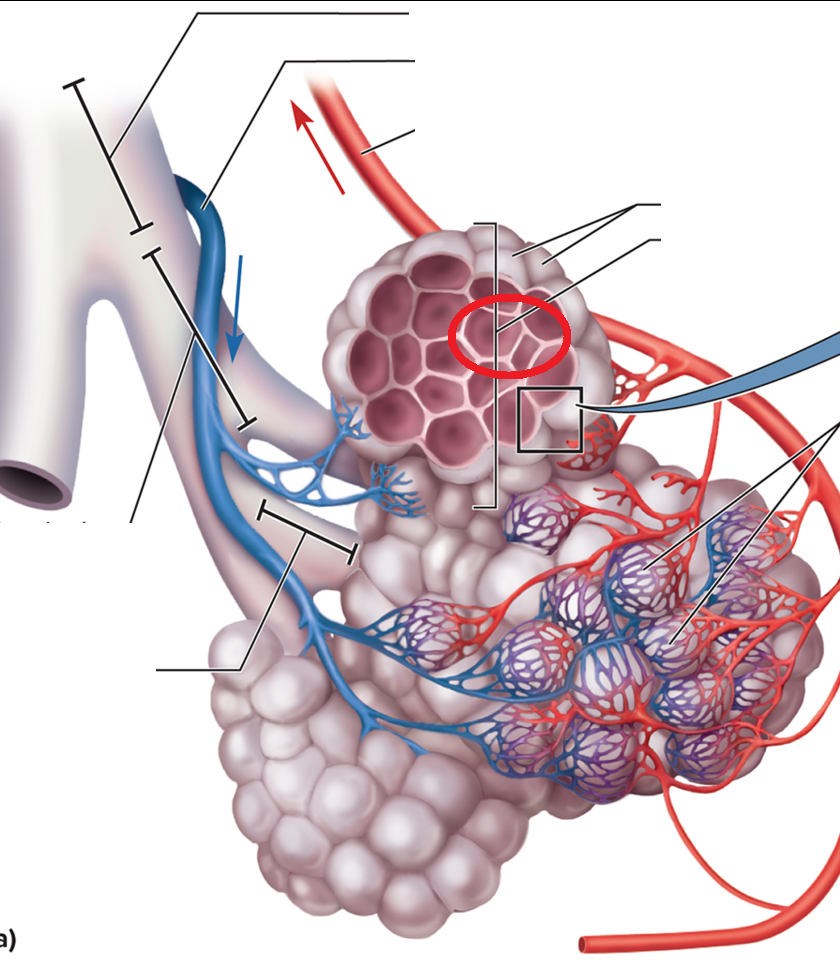

Trachea and Bronchial Tree

Carina T

Tracheal bifurcation T

Main bronchi BT

Lobar bronchi BT

Segmental bronchi BT

Bronchiole BT

Terminal bronchiole BT

resp bronchiole

Alveolar duct BT

Alveolar sac BT

Alveolus BT